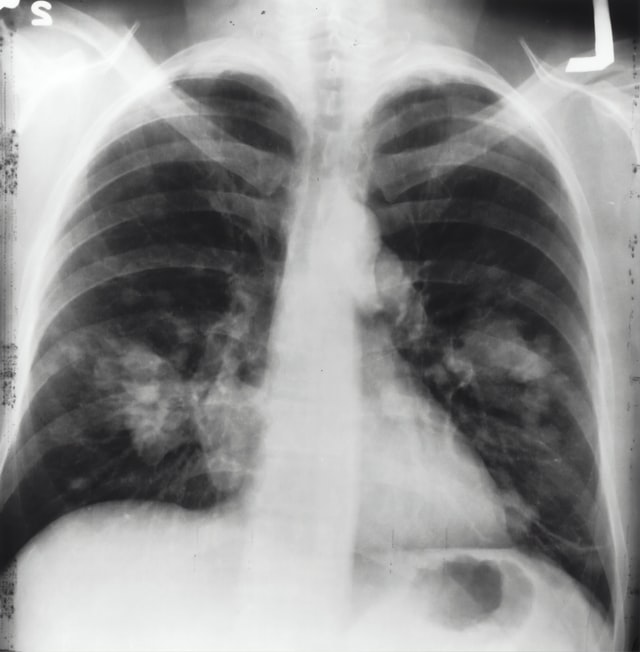

Ilustrasi paru-paru terkena TBC. Foto: unsplash.com